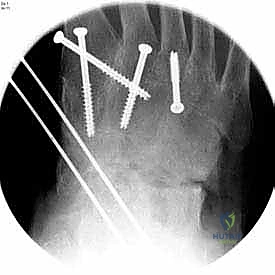

بعد التأكد من الوضعية المثالية للعظام، يتم تثبيتها بقوة باستخدام مسامير معدنية مجوفة من التيتانيوم (Cannulated Screws) أو شرائح معدنية خاصة. يتم إدخال المسامير تحت توجيه الأشعة السينية المباشرة (Fluoroscopy) داخل غرفة العمليات لضمان الدقة المتناهية. هذه المسامير تضغط العظام معاً وتمنع أي حركة حتى يحدث الالتئام التام.